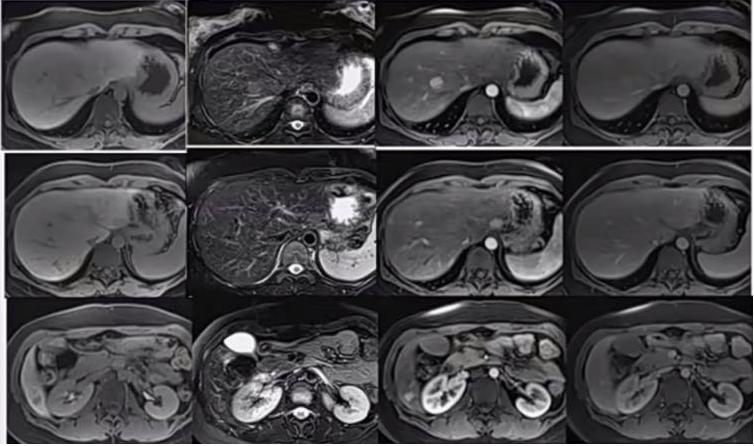

2021.01.09上腹部MRI平扫+强化(图8)。原单位MRI报告:1、肝内多发结节,考虑占位性病变可能性大,不除外恶性。2、脂肪肝。3、脾大。

图8